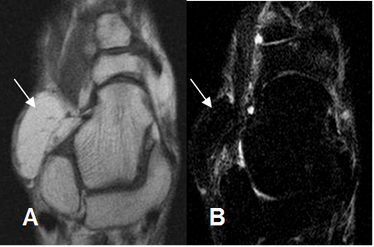

Fig 109. Sindrome del seno del tarso.

A: RM coronal en T1 y B: RM coronal en STIR. Lesiones osteocondrales en la articulación subtalar, (Flechas delgadas), con extensión de los cambios inflamatorios a la grasa del seno del tarso. (Flechas gruesas).